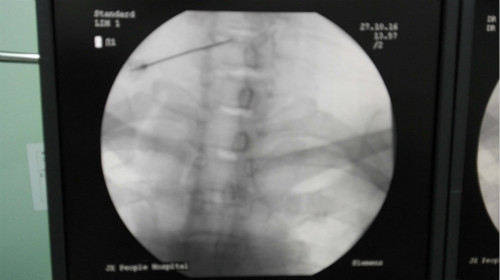

两周后,疼痛科负责人主任医师刘小兵为患者行颈5-6椎间隙穿刺术,也就是我们常说的“低温等离子射频消融术”。术后当天,患者颈部症状基本消失,2天后,左拇指麻木感明显减轻。

据刘小兵介绍,椎间盘突出症传统的治疗方式采用开放手术行髓核摘除术,以达到松解神经根与减压的目的。此方法创伤大、术后恢复时间长,还可能并发粘连、瘢痕等神经性疼痛。而低温等离子射频消融术为微创术,手术创口仅为一1.1mm左右的穿刺针针头大小,能在较低温度下直接汽化髓核组织,同时能够为术者提供触觉反馈,对椎间盘进行精准减压。由于止痛作用显著,术后能持久提高生活质量,明显降低疼痛感,低温等离子射频消融术越来越成为解决此类问题的首选。